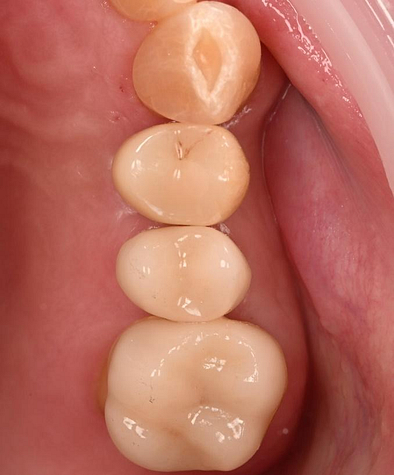

At the final appointment, the crown was securely attached to the implant, resulting in a beautiful, natural-looking restoration.

The implant-supported crown seamlessly integrated with the patient's natural dentition, and the patient reported excellent comfort and function.

A radiographic assessment confirmed the proper integration and positioning of the implant.